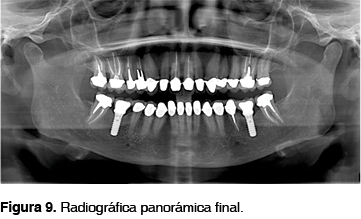

Los implantes reemplazaron los dientes ausentes de manera individual. La paciente se siente satisfecha ya que al sonreír no existe exposición excesiva de encía, cumpliéndose así con todas las expectativas tanto funcionales como estéticas (Figuras 8, 9 y 10).